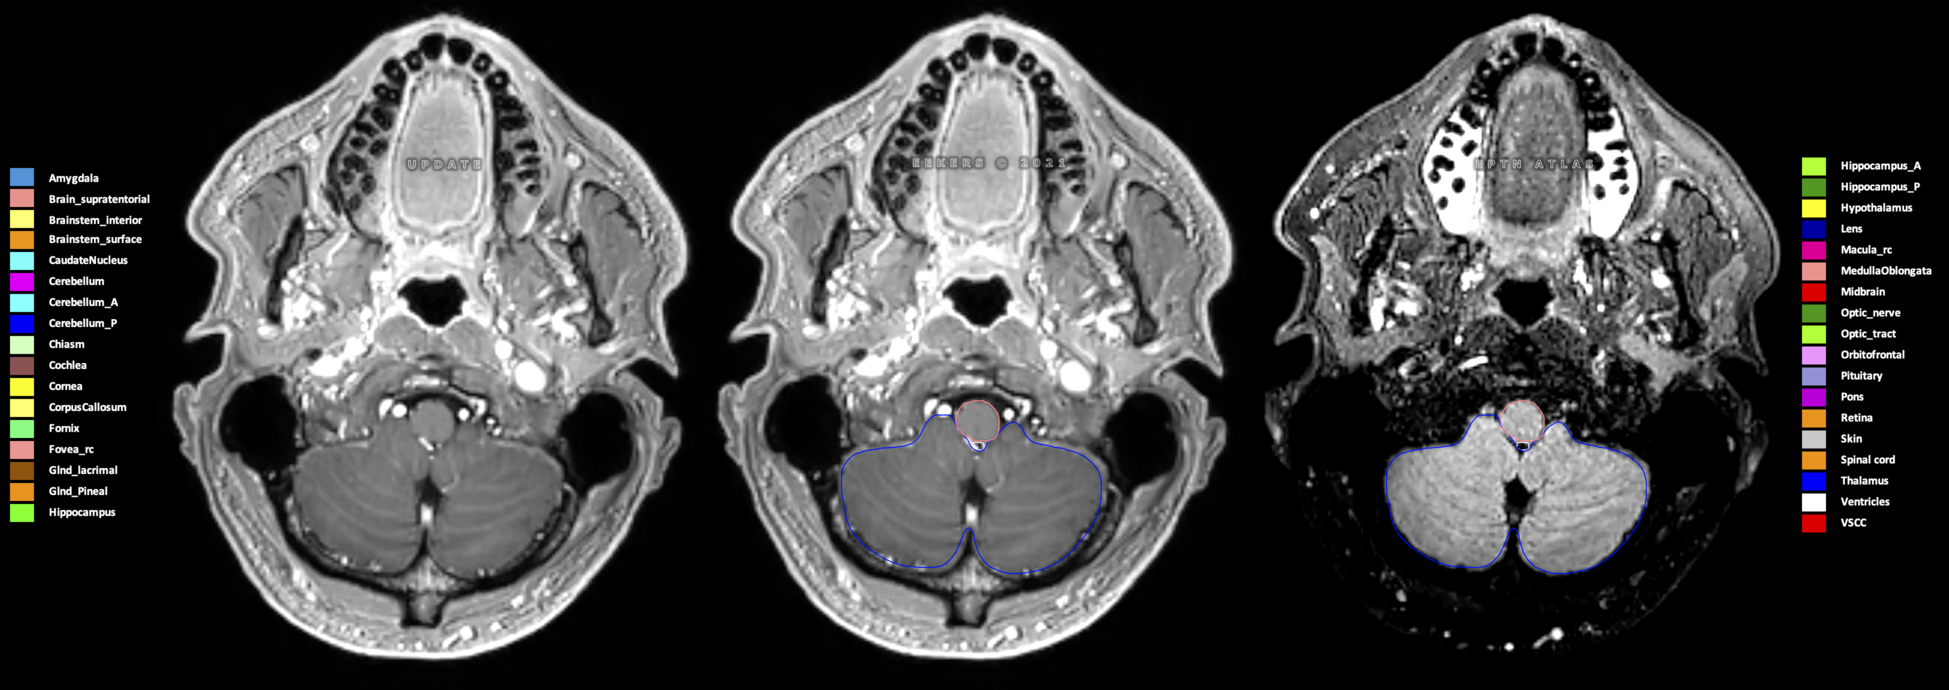

Eekers et al. have published an international neurological atlas for contouring of organs at risk in consensus with the European Particle Therapy Network (EPTN) in 2018 and an update in 2021. The purpose of this consensus atlas is to decrease inter- and intra-observer variability in delineating OARs relevant for neuro-oncology.

Included are all OARs known to be relevant for radiation-induced toxicity in neuro-oncology: brain, brainstem (midbrain, pons, medulla oblongata), chiasm, cerebellum (anterior & posterior), cochlea, cornea, hippocampus (anterior & posterior), hypothalamus, lens, lacrimal gland, optic nerve, pituitary, skin, and vestibular & semicircular canals. To further facilitate research on cognition, vision and radiological changes after irradiation of the brain, potential clinically-relevant OARs are included: amygdala, caudate nucleus, cerebellum (anterior & posterior), corpus callosum, fornix, macula, optic tract, orbitofrontal cortex, periventricular space (PVS), pineal gland, and thalamus.

Three-dimensional delineation of the 25 consensus OARs for neuro-oncology are shown on CT (WW/WL 120/40, 3000/600), 3T MR images, (T1Gd, T2FLAIR 1mm) and 7T MR (MP2RAGE 0.7 mm). All are presented in transversal, sagittal and coronal view.